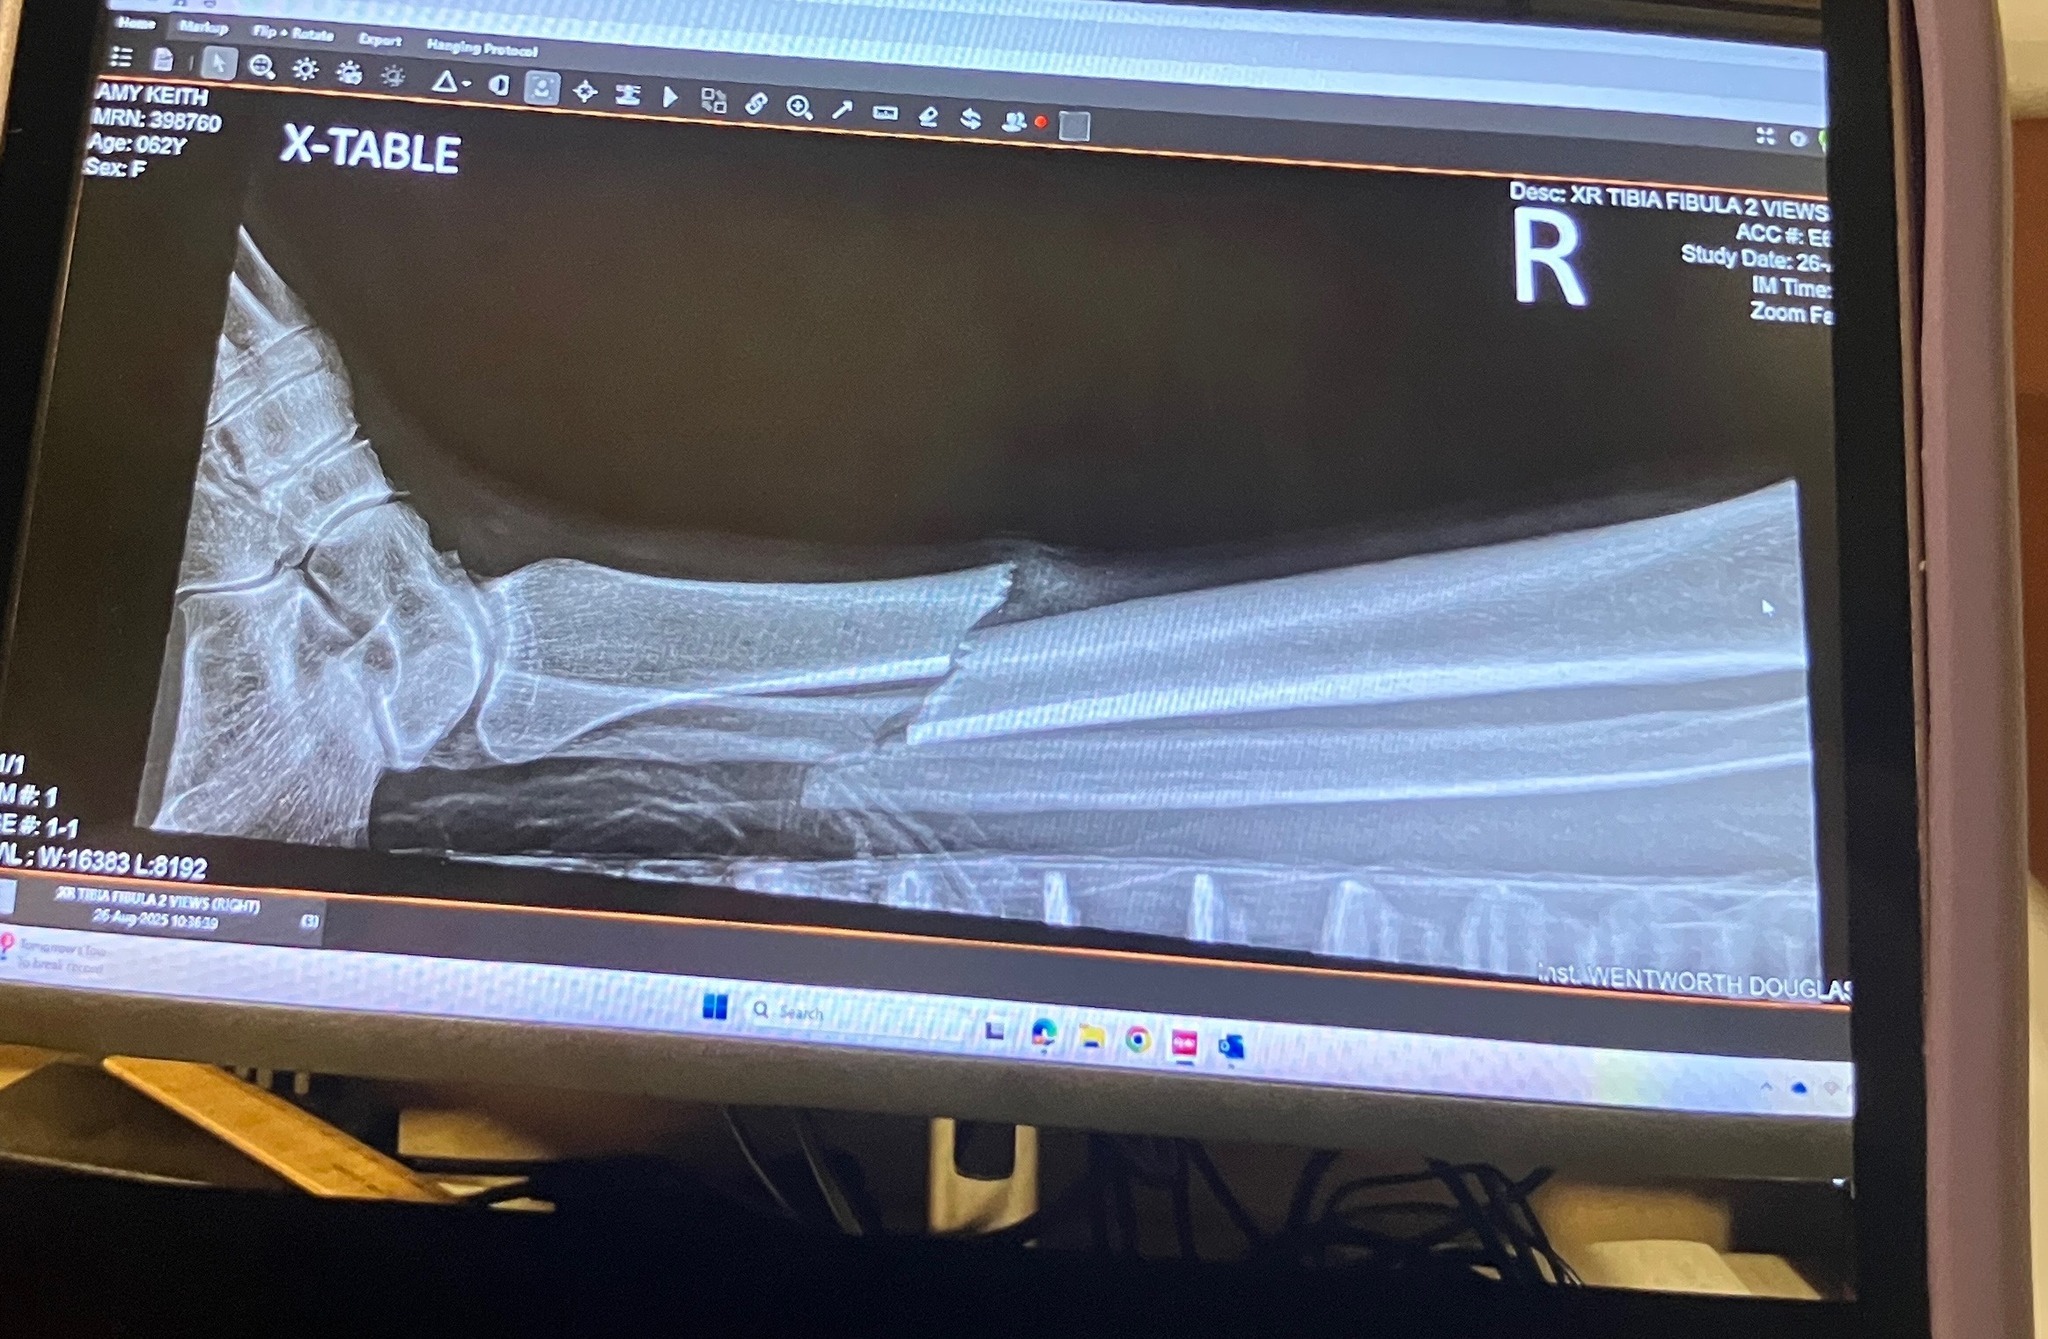

there i was, out on an epic early morning trail ride with a couple of stablemates, when one of their horses fired a hoof out and got me in the shin. i'm speculating the bugs were pissing her off and she didn't really know my horse. no sense getting mad about it, i'ts done. i actually quite like the mare. i knew instantly it was broken. after an initial 'fight' response by my horse, she got a grip and carried me back to the barn, like the wounded soldier i was. she's used to sidling up to our mounting block for me to dismount, so that wasn't weird for her. i swung my bad leg over her back, landing on my good one. with considerable assistance, i got into a car and was transported to the ER at Wentworth Douglass Hospital.

they called me a blessedly short time after arriving. it was an open wound so surgery had to be immediate. i had not eaten and drank only sparsely that morning so that was good, and there was a good leg doc available. damage control was going well. next thing i know, i'm sporting a titanium rod from knee to ankle with a screw at each end. i am SO grateful for modern medicine and good surgeons, not to mention my beloved barn family, who have been killing me with loving kindness and delicious food since coming home.